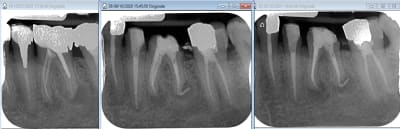

Retraitement de 17 et 16 en 2 temps.

La 17 retraitée en janvier présentait un canal MV en lame de couteau, comme décrit plus haut. La radio n'était pas si affolante que ça quant à la qualité du précédent traitement, et pourtant j'ai sorti des kilos de merde du canal.

La 16 présentait un MV2 distinct, non traité, mais qui ne semblait pas "visuellement" infecté.

La patiente a fait un covid il y a 10 jours, et me décrit au téléphone une récidive de l'infection de 17.

Elle se sent gonflée dans la zone, peut-être faudra-t-il extraire.